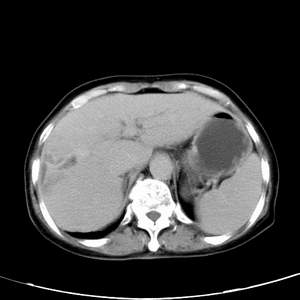

患者,女性,77岁,右上腹胀痛月余。afp正常。ca125升高。即往无肝炎病史。

肝右叶病灶是胆管细胞癌吗?门静脉右支癌栓形成?右侧肾上腺有问题吗?

快进快出符合肝癌表现

病灶强化不均匀,形态欠规整.患者年龄很高.

考虑肝癌

延时后,病变与肝脏呈等密度,先考虑:肝血管瘤.

最后5幅图片是延时7分钟的。门静脉右前支内有充缺吗?如有,肝血管瘤不好解释。

渐进性强化,中间见沙砾样钙化,首先考虑血管瘤

病灶渐进性向心性强化,延时病灶中心见条片状高密度影,局部见肝包膜回缩征,结合病人无肝炎病史,考虑肝右叶胆管细胞癌,门脉右支癌栓形成。